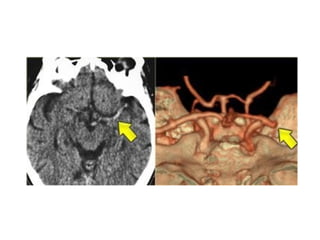

4.Dense MCA sign

• This is a result of thrombus or embolus in

CTA